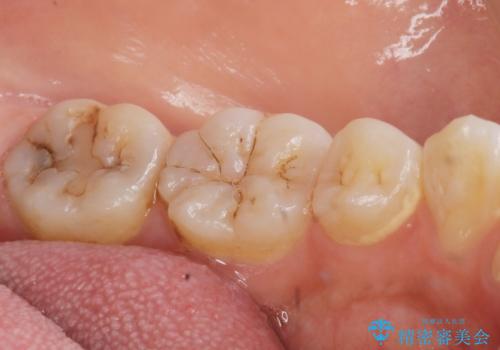

- 奥歯が黒くなっていることを気にされ来院された患者様です。

精査したところ、左下の奥歯にう蝕を認めました。

患者様のご希望により、う蝕を丁寧に除去したのちセラミッククラウンによる補綴治療を行いました。

セラミッククラウンの自然な仕上がりと咬み心地にご満足頂けました。

クラウンの種類:オールセラミッククラウン スタンダード